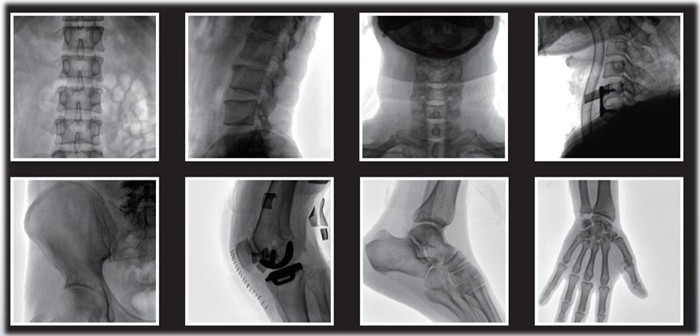

1)小C,骨科手術必備設備,也被稱為骨科小C。作為骨科醫生的眼睛,能在手術中透視實現準確定位,輔助醫生順利、快速、高效完成手術。目前,小C在我國普及率極高,基本上所有二級及以上醫院都標配小C。

小C在骨科的應用是全方位的

2)中C,學名外周介入C形臂(Peripheral Interventional C-Arm)。與小C相比,中C不僅大幅提高了X射線系統功率,更重要的是增加了減影等血管機相關功能,基本可以完成80%的介入手術需求,主要應用在周圍血管科、消化內科、婦科、整形科等領域。